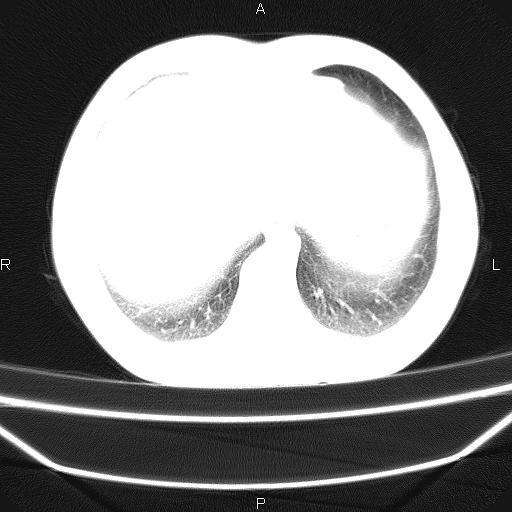

标题: CT26599:男,40岁。间断发热,咳嗽二十余日。体温最高达38.9 [打印本页]

标题: CT26599:男,40岁。间断发热,咳嗽二十余日。体温最高达38.9

患者,男,40岁。间断发热,咳嗽二十余日。体温最高达38.9° 在当地诊所抗炎治疗三天后体温降至正常,患者自行停药。今又发热。胸片示,左下肺阴影。

标题: 左下肺片状高密度影

左下肺片状高密度影,境界模糊,密度不均,考虑感染性病变可能性大,建议抗炎治疗后复查。左肺门增大,不除外占位性病变,必要时支气管镜检。